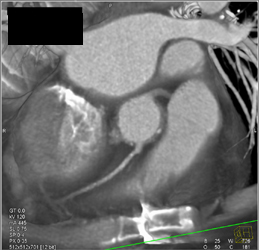

Diagnosis

Stent in LAD